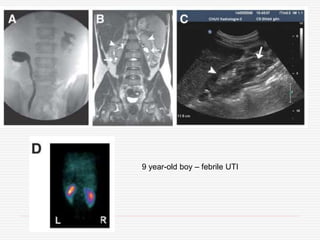

6/12 old boy,febrile UTI by age of 2/12, normal ultrasound and VCUG

9 year-old boy– febrile UTI